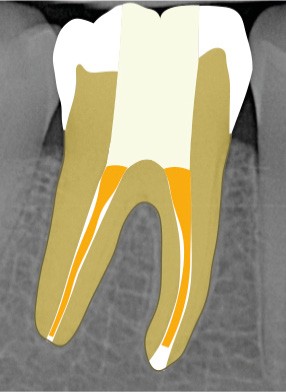

13. si possible, mise en place d’un champ opératoire sur la dent concernée, de sorte à isoler la zone de perforation de toute humidité (fig. 2) ;